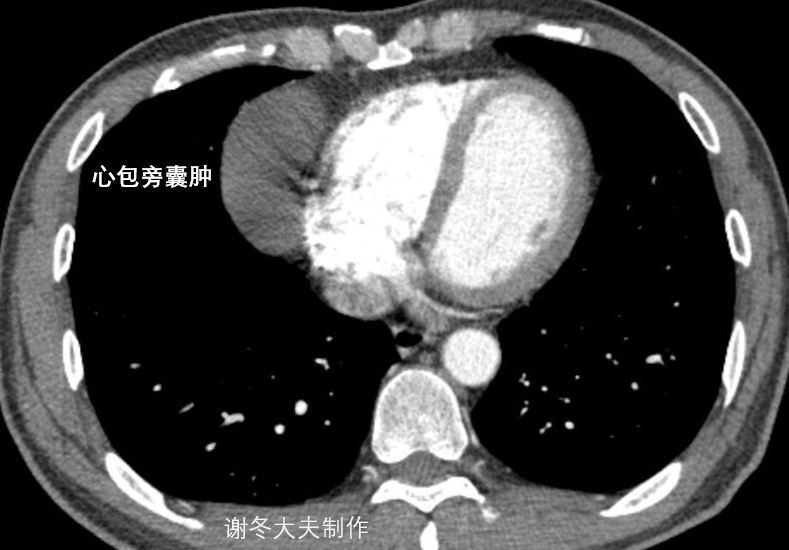

6.谢大夫,这个纵隔占位,是胸腺瘤吗?

回答:这是一个心包囊肿,不是胸腺瘤,但这个只能术中探查才能鉴别诊断。